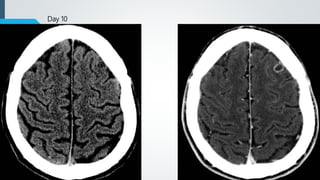

CT findings

 Early

 Patchy, ill-defined, low-density edema with small foci of

hyperdense hemorrhage

 24-48 hours

 Edema, hemorrhage and mass effect often increase

 New foci of edema and hemorrhage may occur.

 Chronic

 Become isodense (at 2 weeks ) then hypodense

 Encephalomalacia with volume loss (at 1 month)

 Repeat CT recommended if initial exam negative but symptoms persist for

24-48 hours.

Day 0 Day 1

Day 10